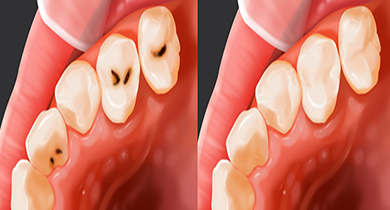

대개 잘 보이지 않는

한두개의 점 모양

급격한 온도차에

의한 통증 발생

온도차 뿐 아니라

음식을 먹을 때 통증 발생

신경조직과 뿌리

끝까지 진행된 상태